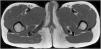

A 9-year-old Moldovan girl with no personal history of interest was referred from pediatrics for left vulvar hypertrophy that had developed over the preceding 6 months and had not responded to topical treatment with corticosteroids and antifungals. The patient reported no local trauma and had not undergone abdominal surgery. The hypertrophy was not accompanied by vaginal exudate and was completely asymptomatic. The patient had maintained excellent general health at all times. Physical examination revealed clear vulvar asymmetry. The left labium majus was enlarged and perifollicular accentuation and mild scaling were evident. No other local inflammatory signs or associated extragenital skin alterations were observed. On palpation the affected area had a soft consistency similar to that of the contralateral labium majus. No palpable subcutaneous lesions were detected. Examination of the rest of the genital area revealed no findings of interest. The patient was prepubertal (Tanner stage I) (Fig. 1). Soft tissue ultrasound showed an unencapsulated, heterogeneous structure with poorly defined margins, with increased vascularity in Doppler mode and no evidence of inguinal hernia (Fig. 2). A T1-weighted magnetic resonance imaging study confirmed the aforementioned findings and ruled out the presence of focal lesions (Fig. 3).

Asymmetric hypertrophy of the labium majus is rare, although its incidence is likely underestimated due to misdiagnosis and a lack of familiarity with this condition. Like asymmetric breast growth, it is considered a physiological response to prepubertal hormonal variations. Its detection is important in order to rule out more severe conditions. The mean age of onset is 8.3 years, and most cases are unilateral.1 Clinical signs consist of enlargement of the labium majus, giving rise to a mass of the same consistency as the surrounding tissue with poorly defined borders; no palpable solid or cystic lesions; and normal skin.2 It is not accompanied by systemic clinical signs and physical examination reveals no other alterations. Diagnosis is based on clinical and radiological findings. Biopsy may also be required in cases that are difficult to diagnose or have a prolonged course, or if an underlying tumor is suspected. The main histological findings are a marked proliferation of fibroblasts, positive staining for estrogen receptor, and an abundant extracellular matrix containing elements commonly found in normal vulvar tissue, including adipocytes, blood vessels, and nerves. Three typical radiological findings are described: heterogeneity; poorly defined borders; and increased vascularity.3 The differential diagnosis includes tumors such as mesenchymal tumors, solitary mastocytoma of the vulva, and aggressive angiomyxoma; congenital vascular and lymphatic malformations; infections such as schistosomiasis; inguinal hernias; Bartholin cyst; and inflammatory processes such as granulomatous vulvitis.1,2,4 In this case an underlying tumor was ruled out based on the results of the imaging studies, in which the bluish coloration typical of vascular malformations was absent, and the ultrasound examination, which showed no compatible findings. An infectious process was not suspected owing to the absence of local discomfort, secretion, and inflammation. Inguinal hernia becomes more pronounced when standing, and was ruled out by radiography. Finally, Bartholin cyst is rare in prepubertal children and granulomatous vulvitis has a recurrent course in the initial stages and is accompanied by progressive induration and, usually, erythema.